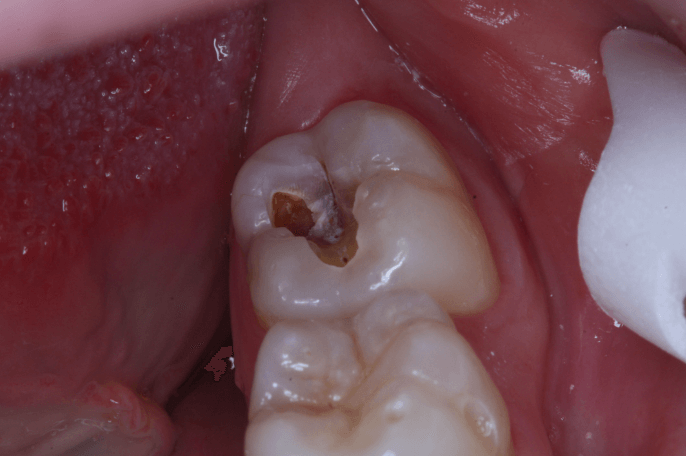

1. Sâu răng khôn và răng kế cận

- Răng khôn mọc lệch hoặc mọc ngầm khiến việc vệ sinh trở nên khó khăn, thức ăn dễ mắc kẹt.

- Đây là môi trường lý tưởng cho vi khuẩn phát triển, gây sâu răng khôn.

- Nếu không điều trị kịp thời, sâu răng có thể lan sang răng số 7, gây tổn thương răng bên cạnh.

- 👉 Theo khuyến cáo của bác sĩ YEN DENTAL, trong đa số trường hợp, nhổ răng khôn là giải pháp hiệu quả và triệt để nhất.

3. Sâu răng và hôi miệng

- Tích tụ thức ăn và vi khuẩn quanh răng khôn khiến răng số 7 hoặc răng khôn bị sâu.

- Viêm nhiễm kéo dài là nguyên nhân gây hôi miệng dai dẳng, khó cải thiện nếu răng khôn mọc sai vị trí không được xử lý.

Răng khôn bị sâu

- Răng khôn nằm sâu trong cùng cung hàm nên rất khó vệ sinh, thức ăn dễ bị nhồi nhét.

- Vi khuẩn phát triển gây sâu răng, ê buốt, đau nhức.

- Thực phẩm quá nóng, lạnh hoặc cứng có thể làm men răng yếu, răng khôn dễ nứt, mẻ, tạo điều kiện cho vi khuẩn xâm nhập.